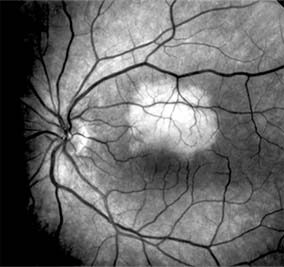

Figure 10-4

Figure 10-4: Flower-petal pattern of fluorescein dye in a patient with cystoid macular edema after cataract surgery.

Retinal edema involving the macula may be associated with a variety of intraocular inflammatory diseases, retinal vascular diseases, intraocular surgery, inherited or acquired retinal degenerations, medications, macular membranes, or unknown causes. Macular edema may be diffuse, with nonlocalized intraretinal fluid causing thickening of the macula. When edema fluid accumulates in honeycomb-like spaces of the outer plexiform and inner nuclear layers, it is called cystoid macular edema. On fluorescein angiography, fluorescein dye leaks from the perifoveal retinal capillaries and accumulates in a flower-petal pattern about the fovea (Figure 10-4).